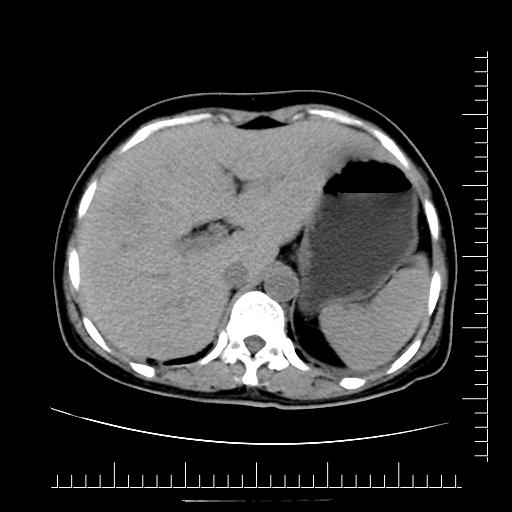

CT49735:高血压、糠尿病多年

本帖最后由 cefcmj 于 2015-1-11 21:05 编辑 肝内占位病变

像肝脓肿 腹膜后淋巴结液化

多发肝脓肿

肝脓肿可能性大

先考虑肝脓肿,其次肝癌

病人发烧吗?考虑感染性病灶,肝脓肿?